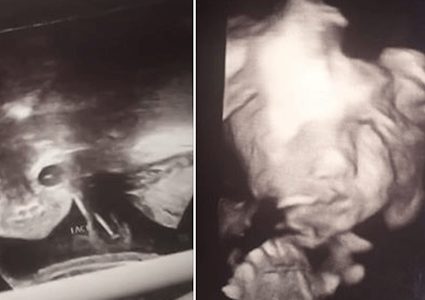

أثارت صورة "الجنين الشيطان" حسب تعبير الأم، التي انتشرت بشكل واسع على مواقع التواصل الاجتماعي، ضجة كبيرة حول العالم، فضلا عن قلق والديه. ونشرت الأم ...